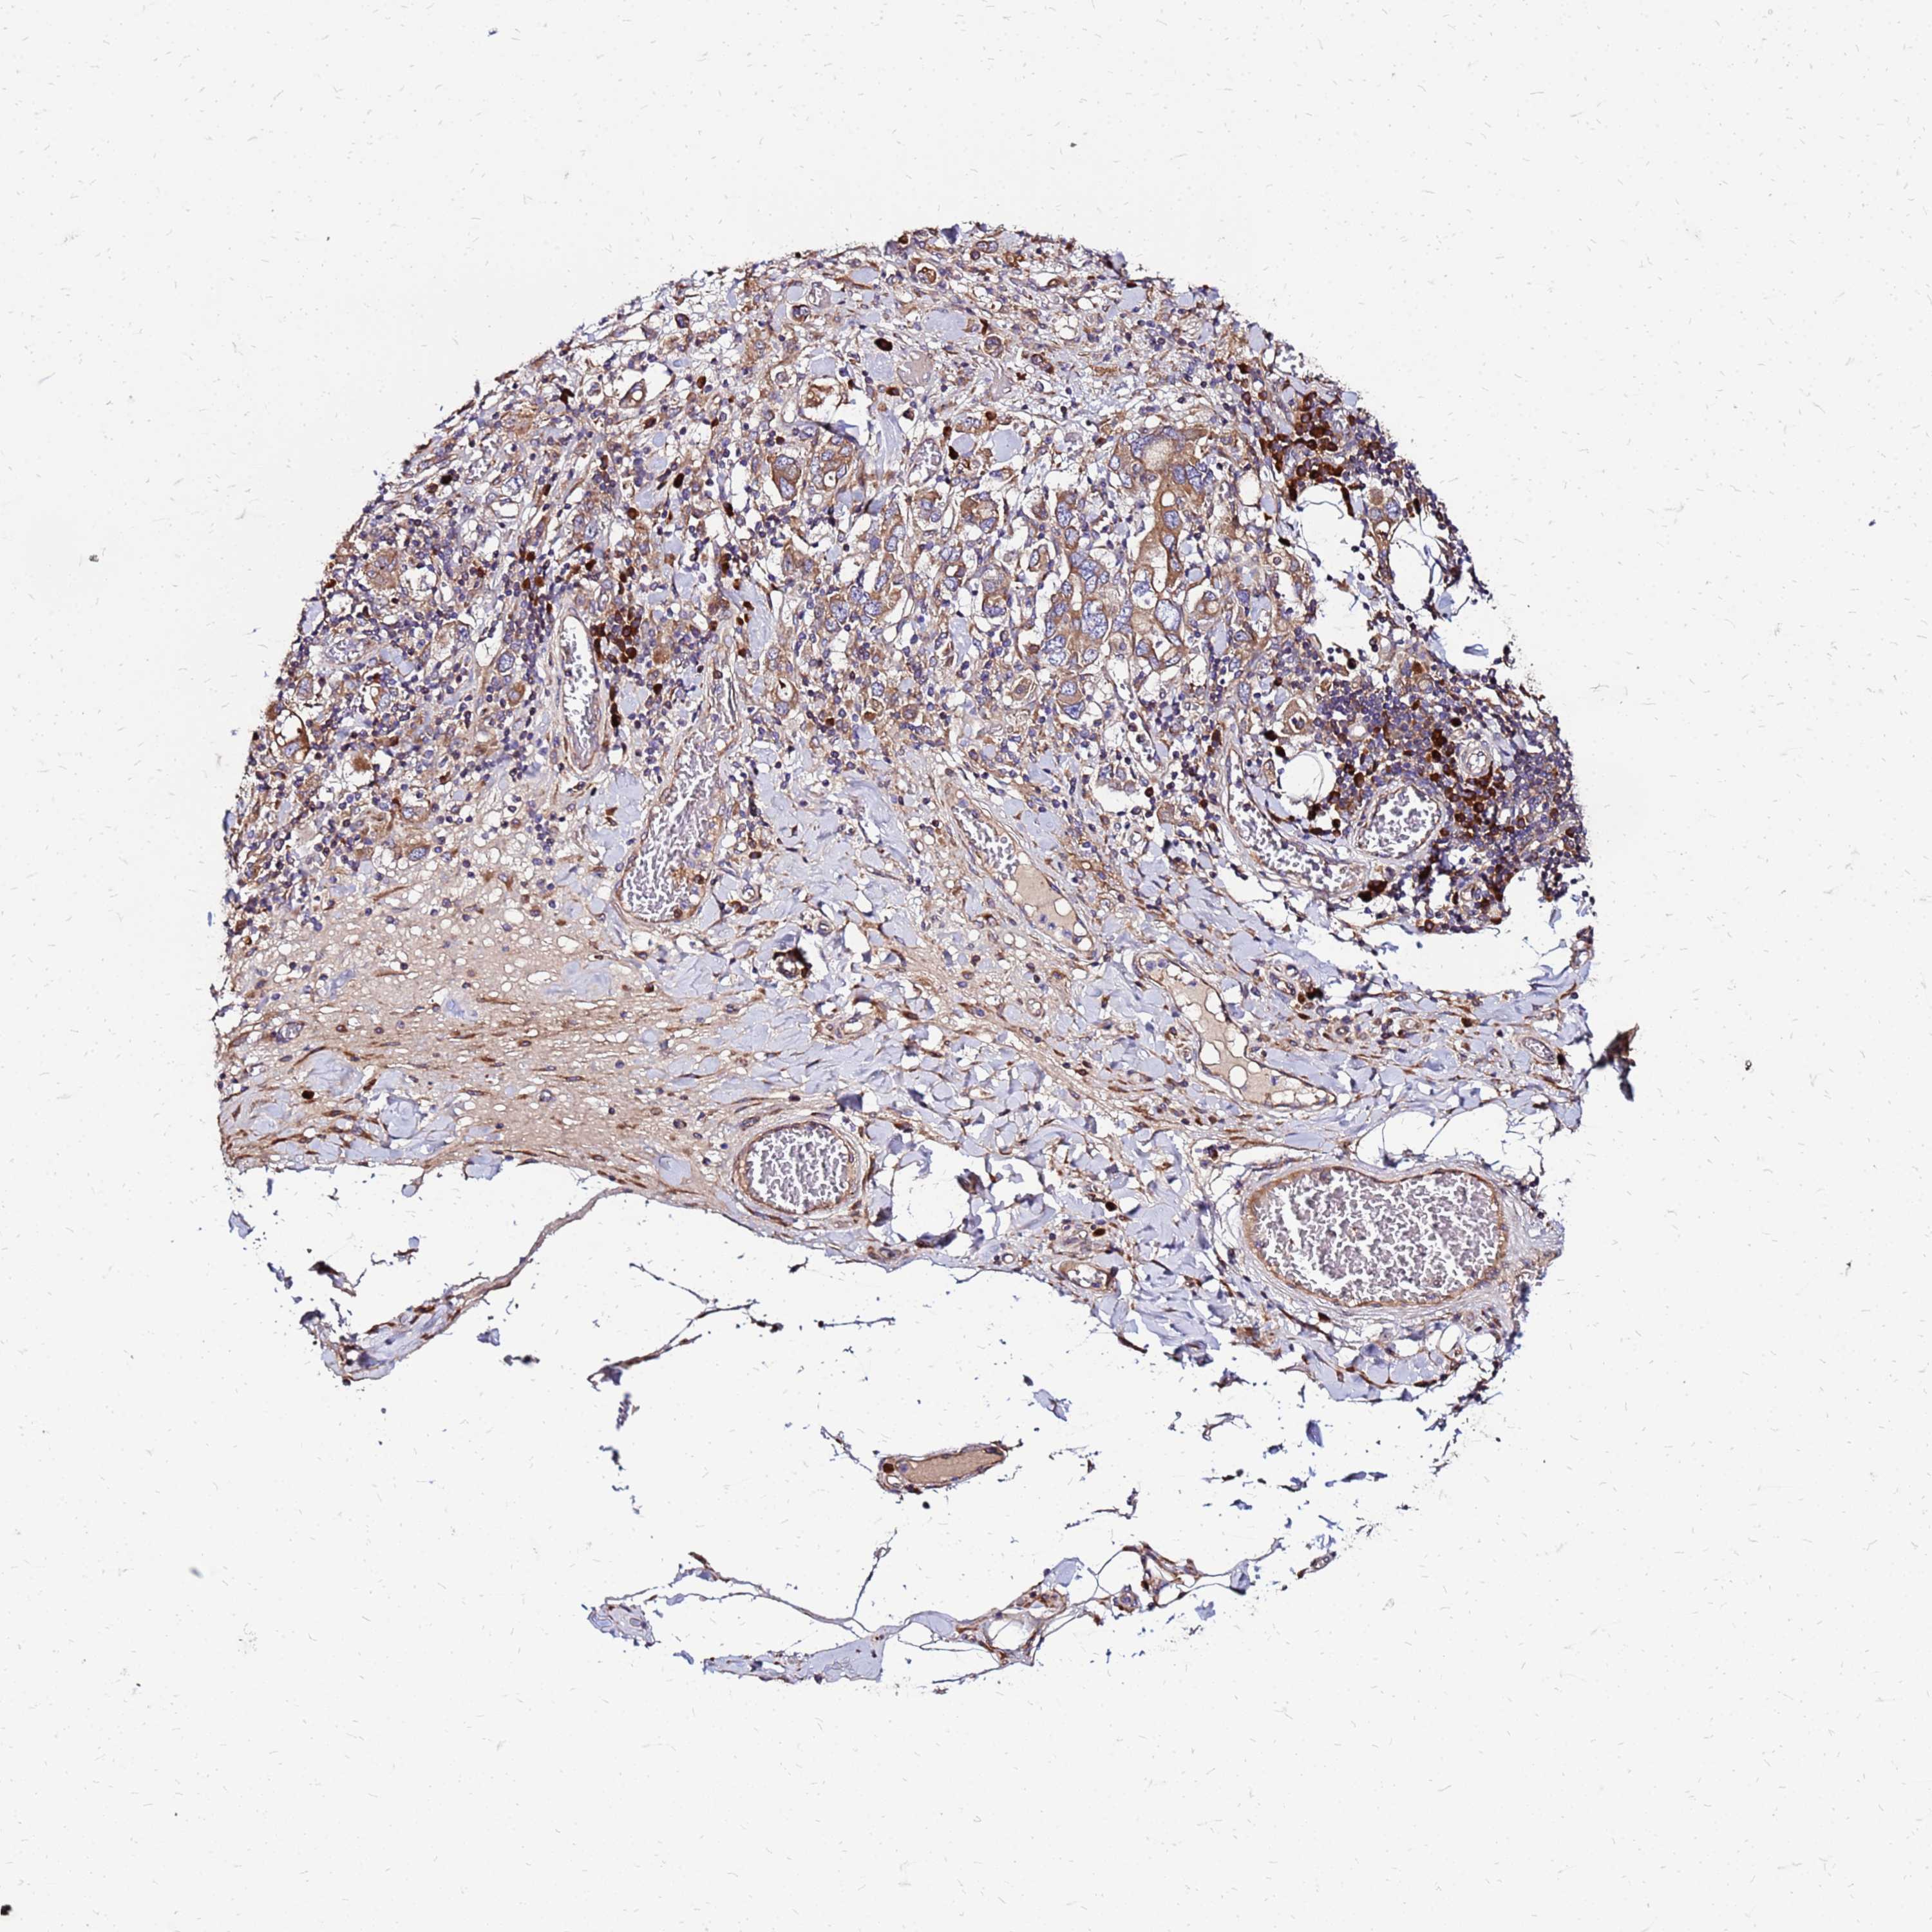

STOMACH CANCER - Protein expressioni

A mouse-over function shows sample information and annotation data. Click on an image to view it in a full screen mode. Samples can be filtered based on level of antibody staining by selecting one or several of the following categories: high, medium, low and not detected. The assay and annotation is described here.

Note that samples used for immunohistochemistry by the Human Protein Atlas do not correspond to samples in the TCGA dataset.

Antibody stainingi

Antibody staining in the annotated cell types in the current human tissue is reported as not detected, low, medium, or high, based on conventional immunohistochemistry profiling in selected tissues. This score is based on the combination of the staining intensity and fraction of stained cells.

Each image is clickable and will lead to virtual microscopy that enables deeper exploration of all samples and also displays staining intensity scores, fraction scores and subcellular localization as well as patient and tissue information for each sample.

Antibody HPA023038

Staining

High

Medium

Low

Not detected

Intensity

Strong

Moderate

Weak

Negative

Quantity

>75%

75%-25%

<25%

None

Location

Nuclear

Cytoplasmic/membranous

Cytoplasmic/membranous,nuclear

Adenocarcinoma, NOS